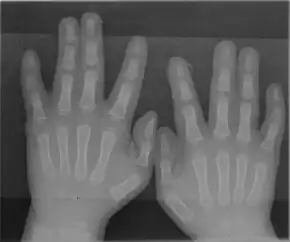

Andersen–Tawil syndrome affects the heart by prolonging the QT interval, a measure of how long it takes the heart to relax after each heart beat. This, as in other forms of long QT syndrome, can lead to abnormal heart rhythms such as ventricular ectopy or ventricular tachycardia causing palpitations.[6] The ventricular tachycardia seen in Andersen–Tawil syndrome often takes a form known as bidirectional ventricular tachycardia. The arrhythmias seen in association with the condition can cause sudden cardiac death, but the risk of this is lower than in other forms of long QT syndrome.[1] The physical abnormalities associated with Andersen–Tawil syndrome typically affect the head, face, limbs and spine. Abnormalities of the head and face include an unusually small lower jaw (micrognathia), low-set ears, widely spaced eyes (hypertelorism), a broad forehead and nasal root, a high arched or cleft palate, and a long narrow head (scaphocephaly).[4] Abnormalities of the limbs and spine include an abnormal curvature of the fingers, particularly the fifth finger (clinodactyly), fused fingers or toes (syndactyly), short stature, and a curved spine (scoliosis).[4]

Clinodactyly – abnormal curvature of 5th finger towards 4th finger -

Andersen–Tawil syndrome is generally diagnosed based on symptoms, the findings on examination, and the results of an electrocardiogram.[4] Clinical diagnostic criteria have been proposed which suggest that a diagnosis can be made if two of the following four criteria are met: (1) periodic paralysis; (2) ventricular arrhythmias (frequent ventricular ectopic beats or ventricular tachycardia), a prolonged QT interval when corrected for rate, and/or a prominent U wave; (3) at least two of the following dysmorphic features: low-set ears, wide-set eyes, a small mandible, fifth-digit clinodactyly, and syndactyly; and (4) a family member with confirmed Andersen–Tawil syndrome.[4]